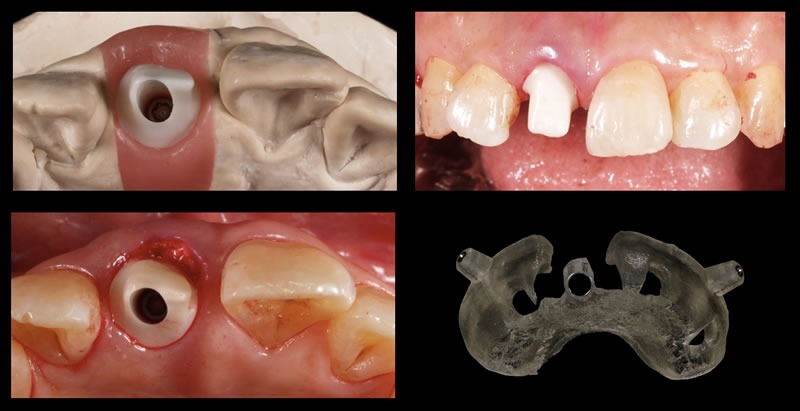

オペの日に間に合うようにハイクオリティな仮歯を用意しておきます

ガイデッドサージェリーと仮歯のSET

インプラント埋入と同時に、あらかじめ用意していた仮歯をSET(即時荷重)